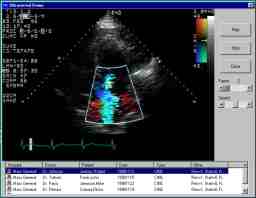

Problem: A manufacturer of cardiology imaging products asked us to develop a video acquisition system to replace an outdated 35mm cine film-based system used to capture images of the heart during catheterizations. The new system needed to provide physicians with the best possible image quality and archive years worth of images. It also needed to be easy and intuitive for lab technicians to operate, as well as robust enough to handle 24-hour-a-day, seven-day-a-week operation. In addition, the system needed to provide all sites with remote dial-up access to facilitate administration, image quality assessment and fault analysis.

Solution: To meet these requirements, Bytes By Design developed a Windows NT-based system which acquires live X-ray video at 30 fps, compresses the loops and archives high-quality DICOM images to a massive ATM networked server. The GUI accepts patient demographics, displays system and network status and snapshots of the procedure. Recorded voice warnings reduce the possibility of errors. The remote administration client analyzes error logs, histograms images and reports error conditions. |

Results: Physicians find the new system extremely effective for timely, life-critical diagnoses. The system's architecture permits collaboration over great distances on patient treatment plans. The technicians find the system streamlines the processing workflow and saves a tremendous amount of time by eliminating the need to load, develop, handle and archive film. |